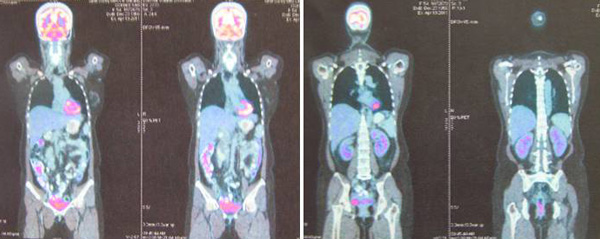

SH said she was well all these years and her progress was monitored by her doctor. About 10 years later, in early 2009, SH developed shortness of breath. She could not lift her left arm. She was tired and lost her appetite. A chest X-ray indicated large left pleural effusion. SH had the fluid in her lung tapped out. A CT scan on 7 January 2009 indicated several subcentimeter nodules in her left lung. The lymph nodes in the left axilla and aortopulmonary window were enlarged. Impression: left pulmonary and pleural metastasis.

SH sought a second opinion from another oncologist at a university hospital. Another CT scan was performed and it also confirmed a metastatic breast cancer with left pleural effusion with small benign liver cysts.

A bone scan done on 29 January 2009 indicated multiple skeletal metastases in the sternum and two ribs on the left side.

In August 2011 SH developed shortness of breath again. A CT scan on 4 August 2011 confirmed presence of mild left pleural effusion. Fluid was tapped out of her lung again.

A bone scan done on 18 March 2011 indicated “sclerotic bone metastases in manubrium showing activity.” SH was told that if Aromasin did not work for her, she would have to undergo intravenous chemotherapy.